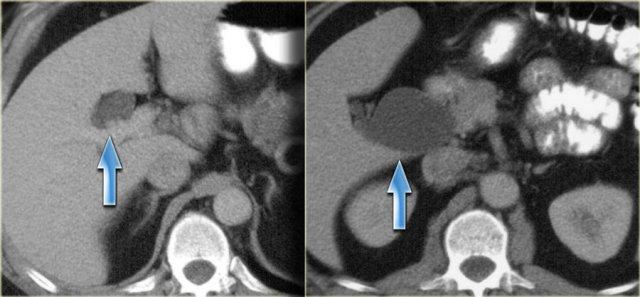

Bên trái là hình ảnh của một bệnh nhân có bệnh nặng hơn.

Chúng ta có thể thấy giãn đường mật nhẹ với hình ảnh gián đoạn.

Bên trái là hình ảnh của một bệnh nhân với các dấu hiệu CT rõ ràng hơn.

Hãy quan sát hình ảnh rồi tiếp tục đọc.

Các dấu hiệu bao gồm:

- Giãn không liên tục

- Thành ống mật dày tại vùng cuống gan

- Hạch bạch huyết to